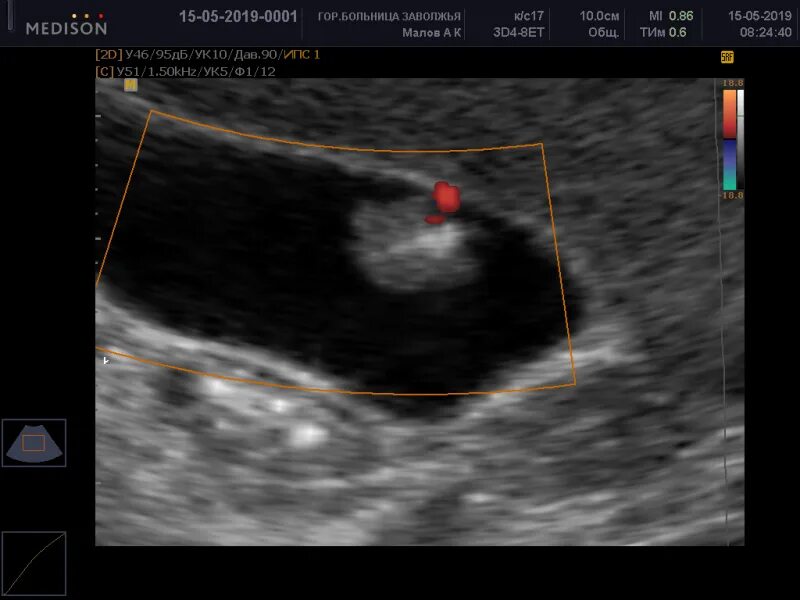

Локусы при цдк что это